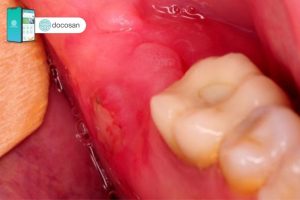

Máu báo thai màu gì là câu hỏi được rất nhiều chị em quan tâm. Máu báo thai thường có màu hồng nhạt, nâu sẫm (màu gỉ sắt) hoặc màu đỏ tươi. Khác với máu kinh nguyệt, máu báo thai ở dạng lỏng, không tạo thành các cục máu đông và không đi kèm dịch nhầy. Do lượng máu rất ít nên máu báo thai hầu như không có mùi gì cả.